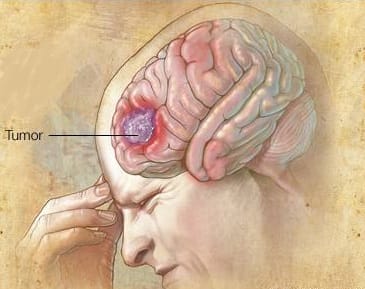

O glioblastoma, também conhecido como glioblastoma multiforme, é um tipo de câncer cerebral altamente agressivo e incurável. Neste artigo, exploraremos diversos aspectos dessa doença devastadora, incluindo sua nomenclatura, epidemiologia, diagnóstico, tratamento, cirurgia máxima segura e opções complementares de tratamento, levando em consideração a situação clínica do paciente. Nomenclatura e Epidemiologia

O conhecido senador dos Estados Unidos John MacCaine, considerado herói da Guerra do Vietnã, é mais uma vítima do Glioblastoma. O Glioblastoma ou GBM é o tumor maligno do cérebro mais comum nos adultos. De uma classificação de 1 (I) a 4 (IV), o Glioblastoma é classificado como IV, ou

Os tumores cerebrais são graduados de 1 a 4 com base nas anormalidades de suas células visto ao microscópio (necrose, proliferação celular etc). O grau 1 é o menos maligno, possuindo menos anormalidades, enquanto o grau 4 é o mais maligno, apresentando mais anormalidades. Um mesmo tumor pode conter células